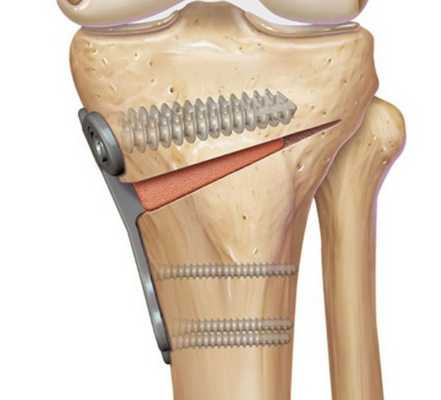

Остеотомия с металлоконструкцией

Далее, участок кости, на котором произведен надрез с помещенным туда костным аутоимплантом, фиксируется титановой пластиной при помощи винтов. Затем доступ ушивается, а конечность иммобилизируется при помощи шины или лангеты. В наложении гипса необходимости нет.